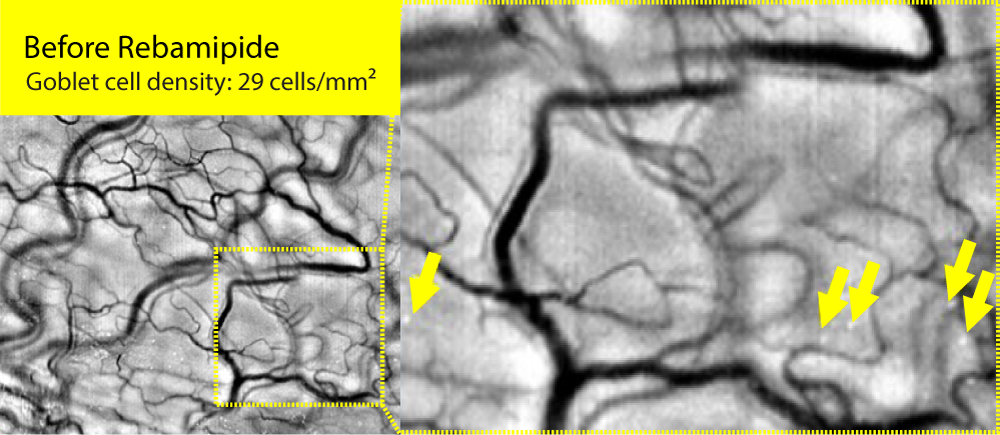

Goblet cells, located in the conjunctival epithelium, secrete the mucin MUC5AC to form the mucin layer of the tear film. They play a key role in maintaining tear film stability and lubricating the ocular surface. When goblet cells are damaged or reduced in number due to inflammation or external stimuli, mucin secretion declines, leading to tear film instability and the onset of ocular surface diseases such as dry eye.

Therefore, goblet cell analysis serves as an important diagnostic biomarker for evaluating the onset, severity, and treatment response of ocular surface disorders, including dry eye disease.

We have developed the world’s first imaging technology for conjunctival goblet cells, a core innovation that enables the diagnosis of various ocular diseases, including dry eye disease. Goblet cells serve as definitive biomarkers for dry eye and play a crucial role in maintaining immune tolerance. This breakthrough technology holds potential for expansion into diagnostics for other